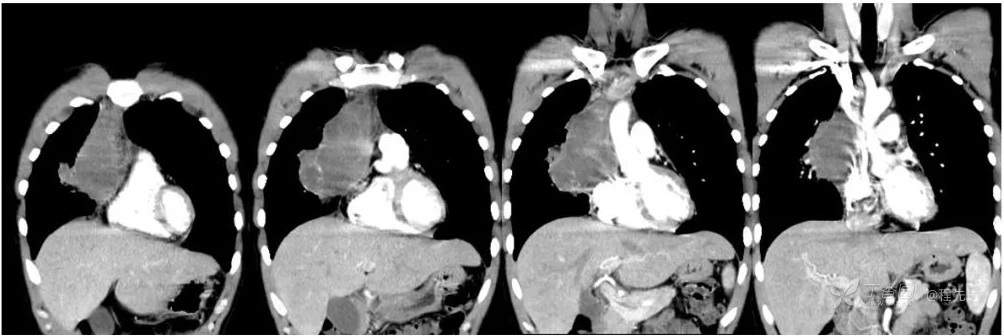

CT增强冠状位